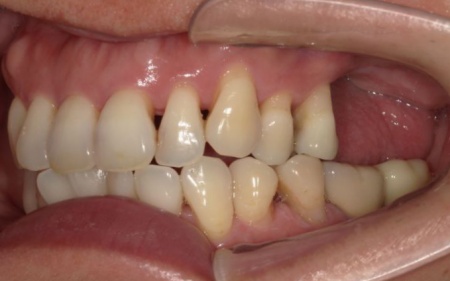

次に、右下に装着されているブリッジを除去してから右下の親知らずを抜き、欠損部(第1大臼歯、第2大臼歯の部分)にインプラントを埋入しました。

また、右下の手前にある奥歯2本(第1小臼歯、第2小臼歯)は、新しく詰め物を作製して噛み合わせと見た目を整えています。

続いて、インプラントに装着する人工歯を作製します。

最後に、完成した人工歯をインプラントに取り付け、噛み合わせや見た目に問題がないことを確認し、治療を終了しました。